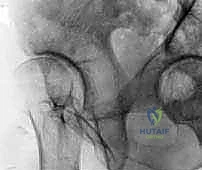

الخطوة الثالثة: القطع العظمي المتعدد (The Osteotomies)

هنا تكمن عبقرية الجراحة. يقوم الدكتور هطيف بإجراء سلسلة من القطوعات العظمية الدقيقة باستخدام أزاميل ومناشير جراحية متخصصة:

1. قطع عظمة الإسك (Ischial Cut): الجزء السفلي والخلفي من الحوض.

2. قطع عظمة العانة (Pubic Cut): الجزء الأمامي من الحوض.

3. قطع عظمة الحرقفة (Iliac Cut): الجزء العلوي من الحوض.

هذه القطوعات تحرر تجويف الحُق بالكامل عن باقي الحوض، مع الإبقاء على الحلقة الحوضية الخلفية سليمة لضمان استقرار الحوض أثناء المشي بعد العملية.

بعد تحرير التجويف، يقوم الدكتور هطيف بتدويره في ثلاثة أبعاد (3D) ليغطي رأس عظمة الفخذ بشكل مثالي. يتم التحقق من التغطية الجديدة باستخدام جهاز الأشعة السينية الفلوروسكوبي داخل غرفة العمليات لضمان الزوايا المثالية.

الخطوة الخامسة: التثبيت (Fixation)

بمجرد الوصول إلى الوضع المثالي، يتم تثبيت التجويف في مكانه الجديد باستخدام مسامير طبية (Screws) مصنوعة من التيتانيوم أو الفولاذ المقاوم للصدأ. هذه المسامير تمسك العظم بقوة حتى يلتئم العظم المقطوع بمرور الوقت (عادة خلال 6 إلى 8 أسابيع).